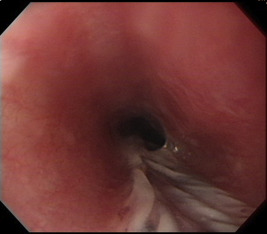

The patients medical history was unremarkable. She did not take any drugs, antibiotics, or caustic material in the past few months. She also denied symptoms of esophageal reflux, acid regurgitation, and epigastric pain. She had no fever. She also had not previously received any medical procedure. On presentation, her vital signs were stable. A physical examination showed no specific abnormality at the head and neck, chest, or abdomen. The patients hemogram, biochemical levels, and cardiac markers were all normal. The chest radiograph and electrocardiogram also appeared normal. She received upper endoscopy in the afternoon on the same day, which showed longitudinal, whitish membrane detached from the posterior wall of the hypopharynx extending to the middle esophagus (30 cm from incisors), which looked like a wrinkled deflated balloon surface (Figure 1 ; Figure 2 ). Unlike infective disease, the lesion was single and regional without ulcerative surface, exudates, or bleeding. The patient’s clinical history and endoscopic scald burn-like mucosal lesion supported the diagnosis of esophageal thermal injury. We did not perform biopsy to avoid further mechanical mucosal injury and bleeding because friable mucosa underneath the detached membrane was seen during the endoscopic procedure. We treated the patient with an oral form of proton pump inhibitor [lansoprazole (30 mg) q.d.] to decrease reflux acid-related injury and educated the patient to eat a cool liquid diet temporally. Three days later, dysphagia and odynophagia improved well and the patient resumed a normal diet. One month later, she was totally free of the aforementioned symptoms. She refused repeat endoscopy and received double-contrast esophagogram 2 months later, which showed normal finding without stricture or remarkable mucosal lesion. The proton pump inhibitor was discontinued after the esophagogram.

Figure 2. Endoscopic view of the esophagus showed a longitudinal, whitish, detached membrane extending to the middle esophagus, like a ruptured bullae. |

Esophageal thermal injury can cause odynophagia, dysphagia, and chest discomfort, but it is rarely considered in the list of causes at initial presentation. In our case, the relevant history and endoscopic finding and rapid clinical recovery support the diagnosis of acute reversible esophageal thermal injury caused by hot food intake. The typical endoscopic finding of esophageal thermal injury is “candy-cane esophagus”, which is characterized by alternating white and red linear mucosal bands [1] . In 2005, Choi et al [2] reported a case of esophageal thermal injury caused by ingestion of hot tea in a 38-year-old woman who underwent upper endoscopy 8 days, 12 days, and 2 months after the onset of odynophagia. Serial endoscopy mainly showed a whitish pseudomembranous lesion in the beginning, which became more similar to the candy-cane appearance 4 days later and finally healed without stricture 2 months later. The authors postulated that during the healing process of esophageal thermal injury, bullae became the whitish pseudomembrane and then presented with the typical candy-cane appearance. In 1996, Javors et al [4] described an esophageal intramural blister that developed after eating hot lasagna. The blister was outlined by a double-contrast esophagogram 5 days after the onset of odynophagia. This report documented the acute bullae formation stage of esophageal thermal injury. In our case, we conducted endoscopy 1 day after the onset of symptoms and the endoscopic finding revealed a linear, ruptured bullae-like lesion. This is the early endoscopic finding of esophageal thermal injury caused by ingesting hot food among the several reported cases [1] ; [2] ; [3] ; [4] ; [5] ; [6] ; [7] .

A literature review of reported cases indicated that the endoscopic manifestation of esophageal thermal injury is decided based on the nature of hot food (liquid or solid), ingestion amount, acute or chronic episodes, and timing of endoscopy after the injury. The sequences of esophageal thermal injury are as follows: a scald injury resulting from mucosal erythema, followed by bullae or blister formation, rupture and necrosis of the mucosa with pseudomembrane, then ulcer with exudate or fragile mucosa, and finally healing with fibrosis. Because we performed upper endoscopy within 24 hours after the onset of the symptoms, the findings of our case only showed a longitudinal, whitish membrane lesion, which was comparable to that of the early stages of the injury with bullae formation. Another category of esophageal thermal injury is caused by radiofrequency catheter ablation of left atrial arrhythmia [8] . The endoscopic findings of this kind of esophageal thermal injury vary from focal erythematic change to focal ulcer. According to Halm et al [8] , esophageal damage may develop if intraluminal temperatures reach ≥41°C.